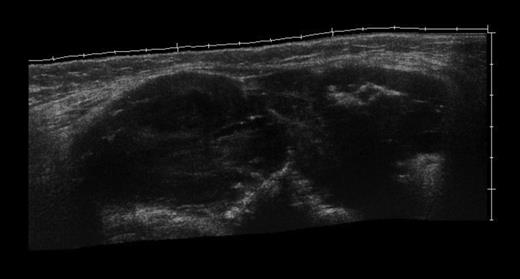

The MRI scan of the right knee (Figs 2 and 3) with gadolinium-enhancement showed a large mass lesion in the posterior aspect of the right knee extending into the popliteal fossa and into the upper third of the right leg having appearance of bursal pathology. Post gadolinium images showed evidence of circumferential rim enhancement but no internal enhancement indicating the presence of a fluid filled lesion. The mass (Figs 4 and 5) measured ∼8.39 × 6.14 × 12.72 cm and was seen between semimembranosus and biceps femoris muscles. There was no evidence of any infiltration of either the sciatic nerve or the popliteal vessels. A likely diagnosis of complicated synovial cyst with a differential diagnosis of haematoma was reported and a provisional diagnosis of Baker's cyst was established.

Post gadolinium-enhanced MRI image showing circumferential lesion.